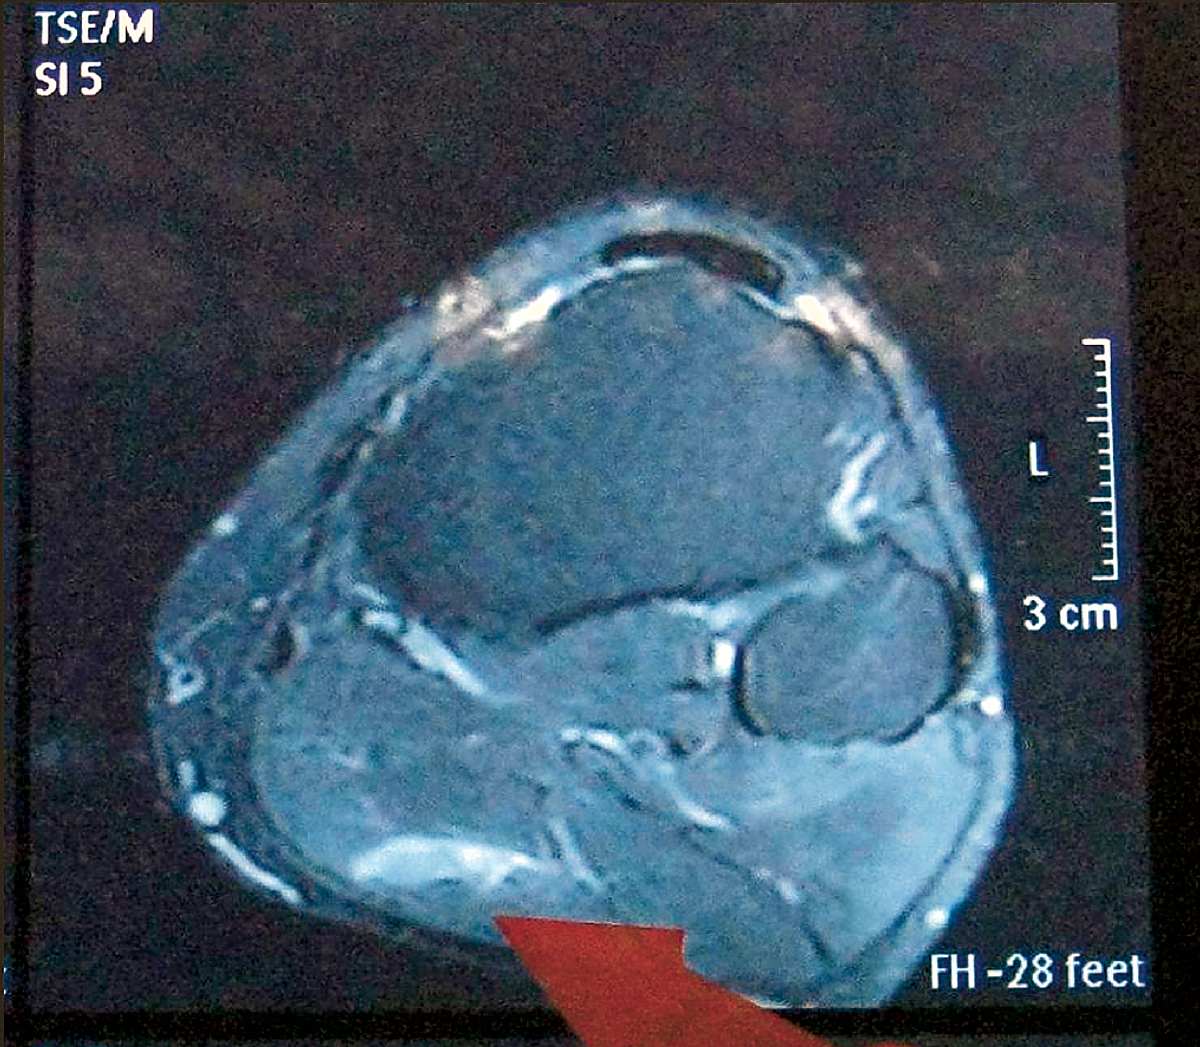

„Eine ausreichende Zeit des Auskurierens ist extrem wichtig bei Muskelverletzungen“, stellt Dr. Thorsten Rarreck, Mannschaftsarzt des FC Schalke 04, klar. Muskel stark überdehnt: Zunächst mal ist aber die Diagnose entscheidend, denn grundsätzlich liegt allen Muskelverletzungen dieselbe Ursache zugrunde: eine Dehnung des Muskels, die über das „normal verträgliche“ Maß hinausgeht. Doch was genau unterscheidet einen Bündelriss von Zerrung oder Faserriss? Was genau passiert dabei in der Muskulatur? Und was sind die möglichen Folgen? Hier gibts die Antworten!!!

"Bei Muskelverletzungen, die ausreichend auskuriert wurden, sollte es nicht zu Folgeschäden kommen", sagt Dr. Thorsten Rarreck. "Ein Muskelbündelriss etwa ist nach meiner Erfahrung frühestens nach sechs bis acht Wochen auskuriert. Bei zu frühem Comback kann es zu neuen, kleineren Verletzungen und dann zu Vernarbungen kommen. Und das bedeutet dauerhafte Schäden!" Zum Beispiel kann dadurch die Sprintfähigkeit eines Spielers dauerhaft geschwächt werden.